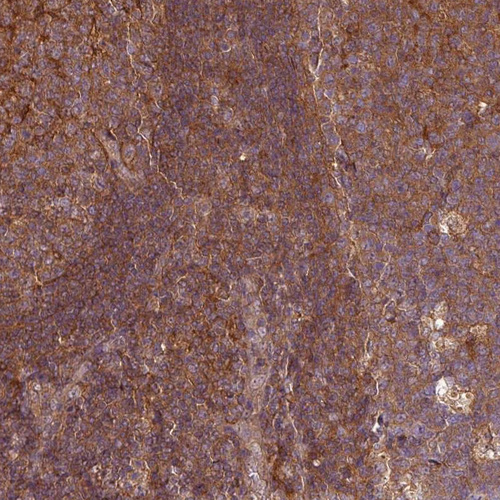

Immunohistochemistry analysis in human tonsil and skeletal muscle tissues using HPA051248 antibody. Corresponding SH3BGRL RNA-seq data are presented for the same tissues.